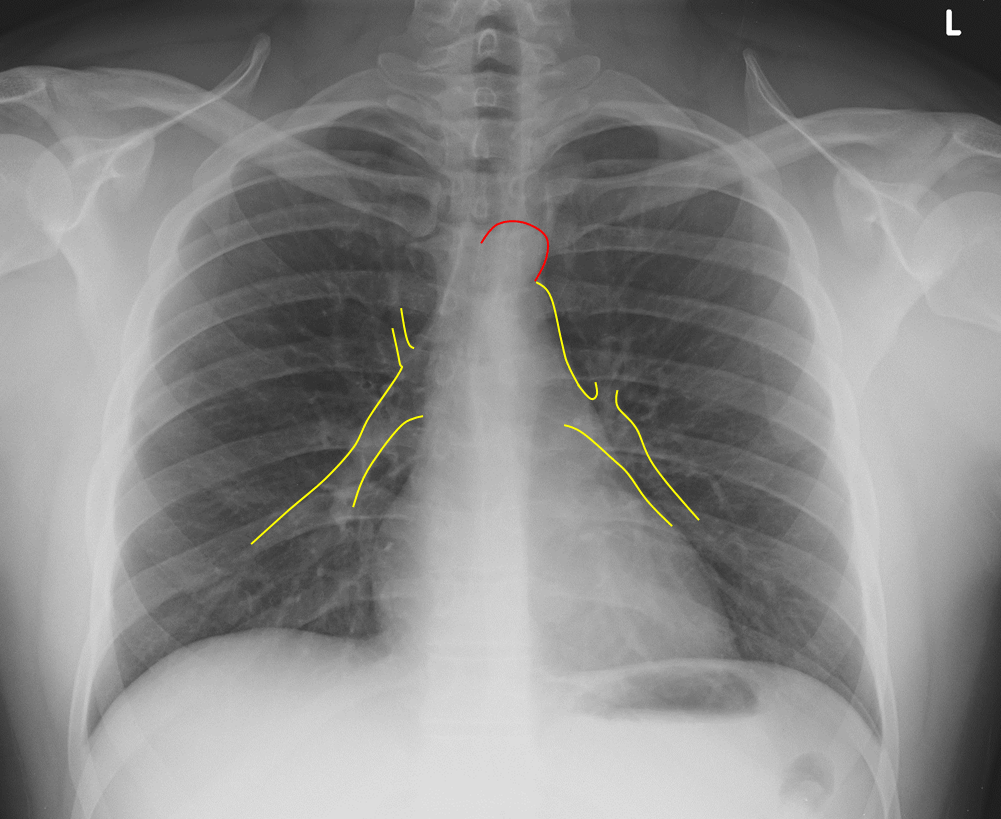

From www.researchgate.net

Chest xray taken on admission showing left basilar atelectasis (red Rv Chest X Ray right heart strain (or more precisely right ventricular strain) is a term given to denote the presence of right ventricular dysfunction usually in the. right ventricle (rv) failure is usually the result of long standing lv failure or pulmonary disease and causes increased systemic venous pressure resulting. the right ventricle (rv) is the most anterior of the. Rv Chest X Ray.